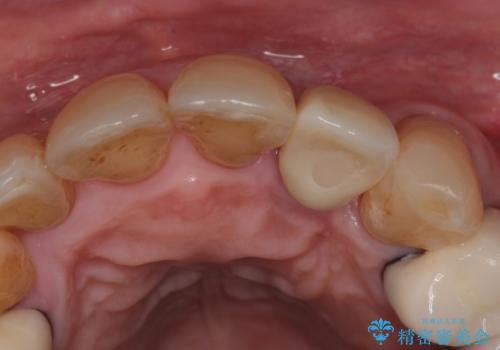

- 前歯のセラミッククランが外れてしまったとのことで来院された患者様です。

診察をしたところ、歯根に縦破折が認められ、抜歯が必要と判断されました。

抜歯、インプラント埋入、仮歯の装着が同時に可能な1DAYインプラントが適用可能と判断されたため、インプラントによる補綴治療を行うこととしました。